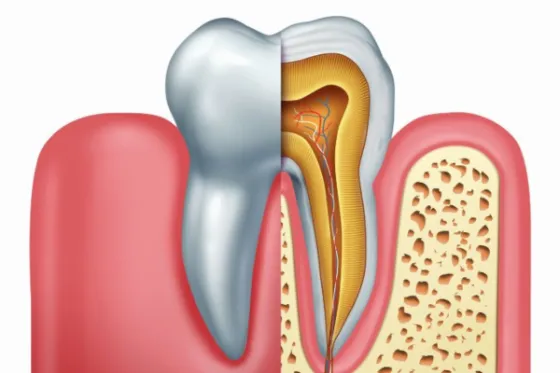

Lečenje kanala korena zuba, odnosno endodontski tretman zuba predstavlja konzervativan način zbrinjavanja oboljenja pulpe (živca) zuba. Ovim terapijskim postupcima se sprečava ekstrakcija zuba i omogućava se da zub ostane u funkciji u dužem vremenskom periodu.

Cilj endodontske terapije je potpuna eliminacija bakterija i njihovih produkata iz unutrašnjosti zuba.

Zanemarivanjem već dubokog karijesa, bakterije i toksini prodiru u komoru zubnog živca, kada dolazi do prve faze zapaljenja ili takozvanog pulpitisa. Kao prvi simptom javlja se osetljivost zuba na toplo i hladno, slatko, a kasnije se mogu javiti i jaki bolovi. Ukoliko se uzrok upale ne ukloni i infekcija ne očisti, može doći do nekroze i gangrene zuba i potpunog odumiranja živca, u koji se dalje naseljavaju drugi sojevi bakterija. Nesanirana gangrena širi se na periapeksno područje, odnosno deo oko vrha korena zuba u kosti. Savremeno lečenje se zasniva na preciznom (mašinskom) čišćenju i oblikovanju kanala korena, temeljnom ispiranju, snažnoj dezinfekciji i preciznom zatvaranju kanalnog sistema. Čišćenje i oblikovanje se sprovodi NiTi (nikl-titanijumskim) instrumentima čija elastičnost omogućava lečenje svih grupa zuba bez obzira na broj korenova i njihovu zakrivljenost.